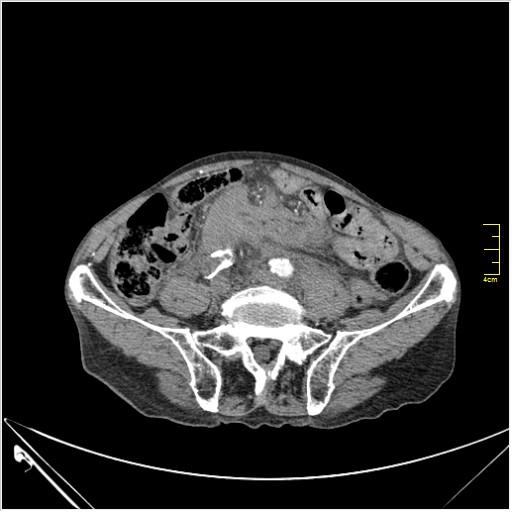

КТ брюшной полости. Мужчина с пальпируемой опухолью в животе

Пациент Т. 64 года, обратился на КТ брюшной полости амбулаторно (!), по направлению семейного врача с диагнозом abdominal mass, буквально: образование брюшной полости.

Huge abdominal aorta aneurism. Simple renal cortical cysts (Bosniak type 1).